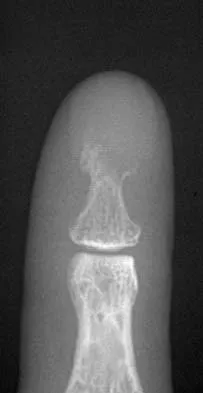

Question 66

A 60-year-old man has pain at the tip of the index finger. A radiograph and biopsy specimen are shown in Figures 40a and 40b. Management should consist of

Explanation

The radiograph and histology findings are most consistent with squamous cell carcinoma. This tumor is best treated with wide surgical resection margins alone in the absence of metastasis; in this patient, management should consist of amputation through the distal interphalangeal joint. The other treatments are not indicated. Soltani K, Krunic A: Non melanoma skin neoplasms, in Vokes E, Golomb H (eds): Oncologic Therapies, ed 2. Berlin, Germany, Springer, pp 646-647.